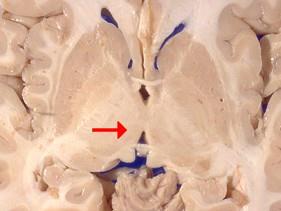

问题 如图箭头所示为大脑哪个部位 ( )

选项 A、松果体 B、中脑导水管 C、豆状核 D、尾状核 E、丘脑 一、单项选择题

答案 E